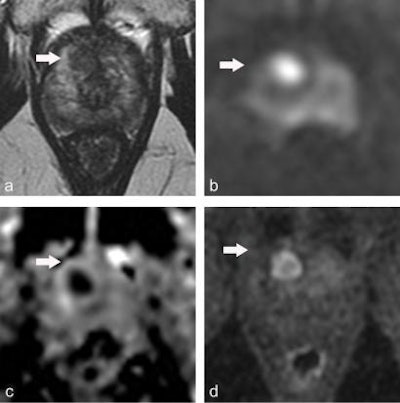

Multiparametric MRI performed in a 59-year-old patient presenting with dysuria and a family history of prostate cancer (a = T2-weighted image, b = diffusion-weighted image at 2,000 sec/mm2, c = apparent diffusion coefficient [ADC] map, d = dynamic image obtained after injection of gadolinium chelates). The rate of prostate-specific antigen was 2.2 ng/mL. Digital rectal examination found a nodule to the left. MRI showed a suspicious lesion with a score of PI-RADS 4 (arrow) in the anterior horn of the right apex. Systematic biopsies (12 samples) were negative. Biopsies targeting the MRI lesion showed prostate cancer with a Gleason score of 8 (4 + 4). Figure courtesy of Dr. Olivier Rouvière, PhD, republished from E-Quotidien des JFR.The MRI-FIRST study -- a prospective multicentric French study -- slightly curbs this enthusiasm. It included 275 patients undergoing a first round of prostate biopsy. All had an MRI scan then systematic biopsies (12 to 14 samples) carried out by a practitioner who had not seen the MRI results, then targeted biopsies (up to two targets and three samples per target) by another practitioner; if the MRI was negative (Likert ≤ 2), the patient only underwent systematic biopsy.